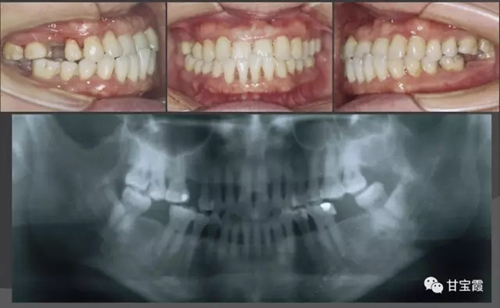

我有一朋友的愛(ài)人,40多歲了,來(lái)診所要求洗牙并且鑲牙三顆,下圖是初診時(shí)拍的X光片和口內(nèi)的頜像,檢查發(fā)現(xiàn)她還有比較嚴(yán)重的牙周病并且伴前牙反咬頜。

經(jīng)過(guò)一系列的檢查和診斷,我做出了矯正牙的治療計(jì)劃,決定首先解除反頜,建立正確的前牙覆頜覆蓋關(guān)系,然后關(guān)閉所有的缺牙間隙不鑲牙。